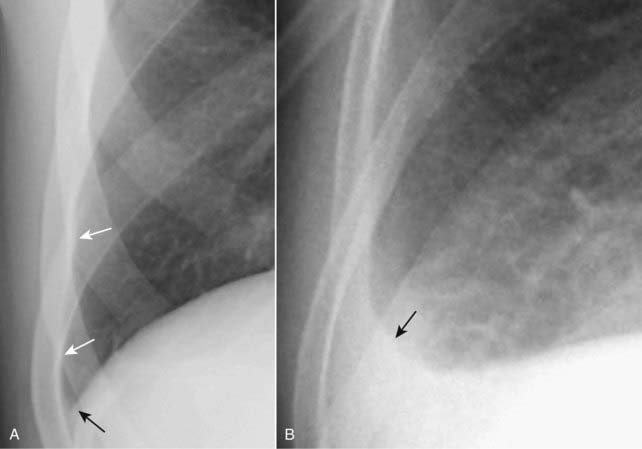

Figure 6-11 Loculated pleural effusion in frontal (A) and lateral (B) projections.

A pleural-based soft tissue density in the right upper lung field represents a loculated pleural effusion (solid black arrows in A and solid white arrows in B). Loculated effusions can be suspected when an effusion has an unusual shape or location in the thorax; for example, the effusion defies gravity by remaining at the apex of the lung even though the patient is upright.

Figure 6-12 Pseudotumor in the minor fissure, frontal (A) and lateral (B) projection.

A sharply marginated collection of pleural fluid contained between the layers of the minor fissure produces a characteristic lenticular shape (solid black arrows in A and B) that frequently has pointed ends on each side where it insinuates into the fissure so that pseudotumors look like a lemon on frontal (A) or lateral (B) chest radiographs (dotted black arrow on A and dotted white arrow on B). Pseudotumors almost always occur in patients with congestive heart failure and, although the pseudotumors disappear when the underlying condition is treated, they frequently return each time the patient’s failure recurs.